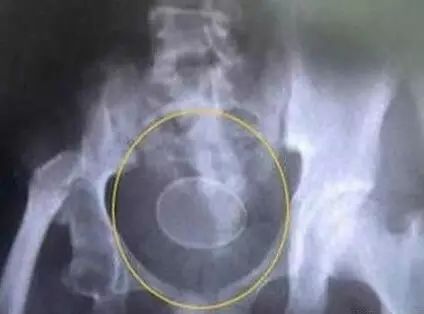

一对20出头的小情侣匆忙来到医院求医,问其原因,竟是亲热时为追求刺激将鸡蛋塞入了女友下面又无法取出了。据了解,就诊时,男子称女伴下腹沉重,感觉有异物,请医生帮忙查看。

在随后的时间里,医生竟从女子的身体内取出了一枚光滑的鸡蛋!在医生询问下,小情侣才支支吾吾地道出实情。

医院妇科医生郭欣欣告诉记者,所幸这枚鸡蛋在体内形态完整,但如果不能及时取出,在人体36℃的温度 下,鸡蛋极容易腐烂,加上细菌成分复杂,很快会发生霉变,造成感染。